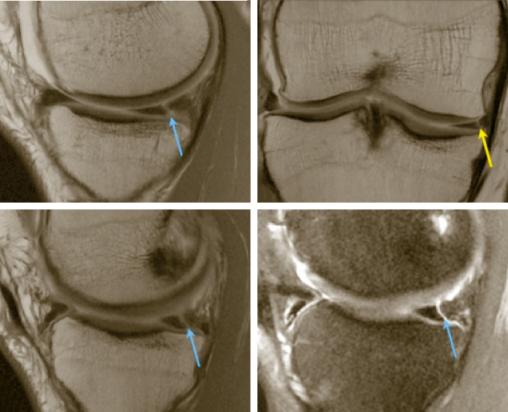

Lésion méniscale médiale traumatique verticale de grade 3

2. Lésion méniscale médiale traumatique verticale de grade 3